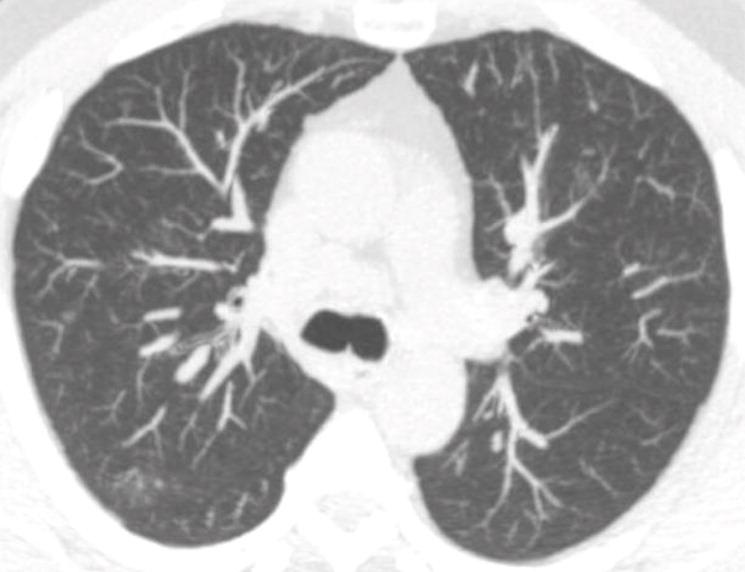

In NELSON, 10.7% of participants had solid, intraparenchymal nodule with volume 50-500 mm^3

10.1% disappeared at followup

May be explained by benign conditions like inflammation commonly showing nodules with a larger diameter